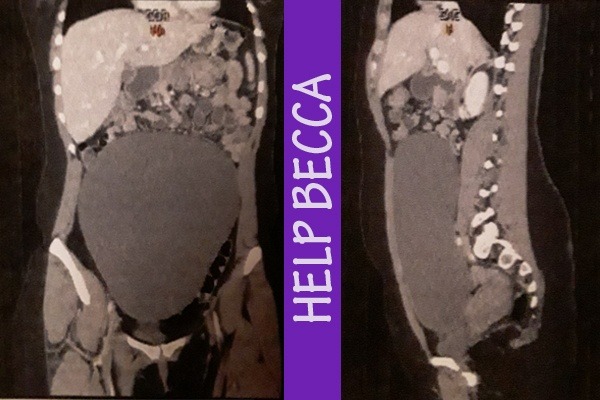

fiance’, Yoong, took her to the ER...what came next was not expected. Becca has an, almost unheard of, MASSIVE Mucinous cystadenoma. This is NORMALLY a common, usually benign, cystic tumor.

What makes Becca’s  different is the shear massiveness of it. It has taken over her entire torso/pelvis. It is larger than a basketball and is a monster taking over her entire body, consuming organs as it grows. This tumor has to be removed  whole along with any absorb organs.

Becca has to  have surgery ASAP. This surgery IS risky. We don’t know what organs have been absorbed (The imaging is unclear) and we do not know how her quality of life will be affected but if we leave it, it WILL kill her. So Surgery IS happening. We need your help. No matter the outcome, she will not be able to return to work for at least 6 weeks. Bills are mounting.